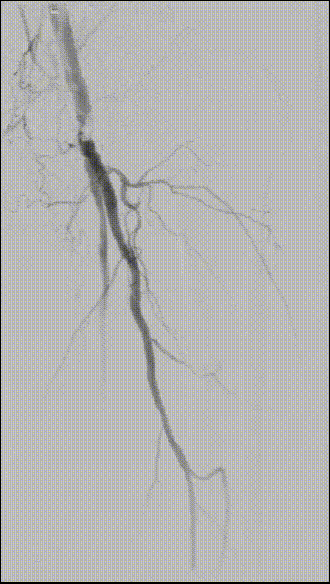

图为:术中造影评估 髂股段

图为:导丝通过病变 置入保护伞 使用Turbohawk定向旋切

图为:股总动脉珊瑚礁病变定向旋切结果股浅动脉段尚未完成定向旋切